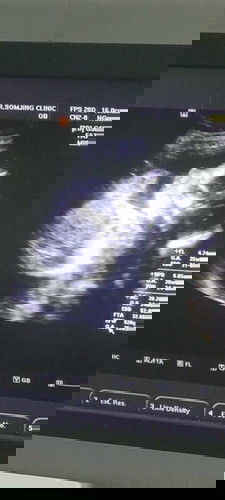

ภาพนี้ตอนน้องด้าย6เดือนกว่า น้ำหนัก820กรัม ลูกน้อยของคุณแม่ท่านอื่นๆ น้ำหนักเท่าไหร่กันแล้วคะ😊❤️